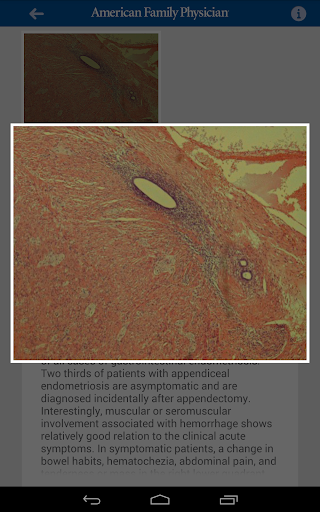

Ideal for primary care learning, the American Family Physician (AFP) Photo Quiz app presents physicians, medical students, and other health care professionals with diagnosis challenges. This app is based on one of the most popular features in AFP, the preeminent medical journal for primary care! Try your skill at diagnosing the condition based on a photograph and a brief clinical scenario. Immediately find out if you answered correctly, and then read the accompanying discussion, which provides pertinent clinical features of the condition, differential diagnosis considerations, and why the other plausible answer choices are incorrect. AFP is a publication of the American Academy of Family Physicians (AAFP).

•Click on the images to take a closer look

•Get the full explanation of correct and incorrect answers